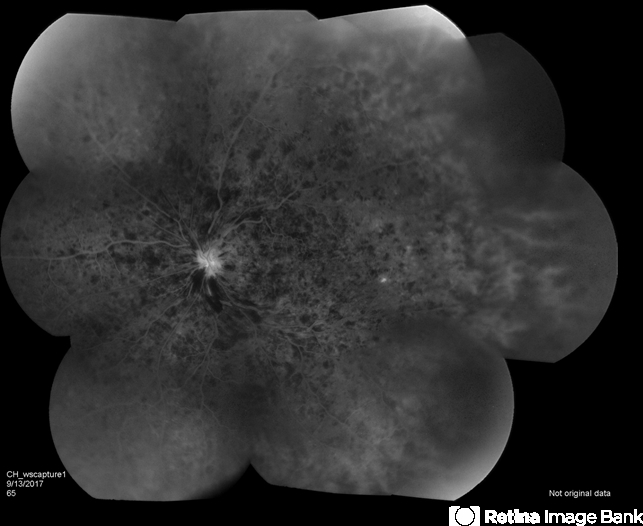

- central retinal vein occlusion (CRVO)

- Fundus camera

- Central retinal vein occlusion.